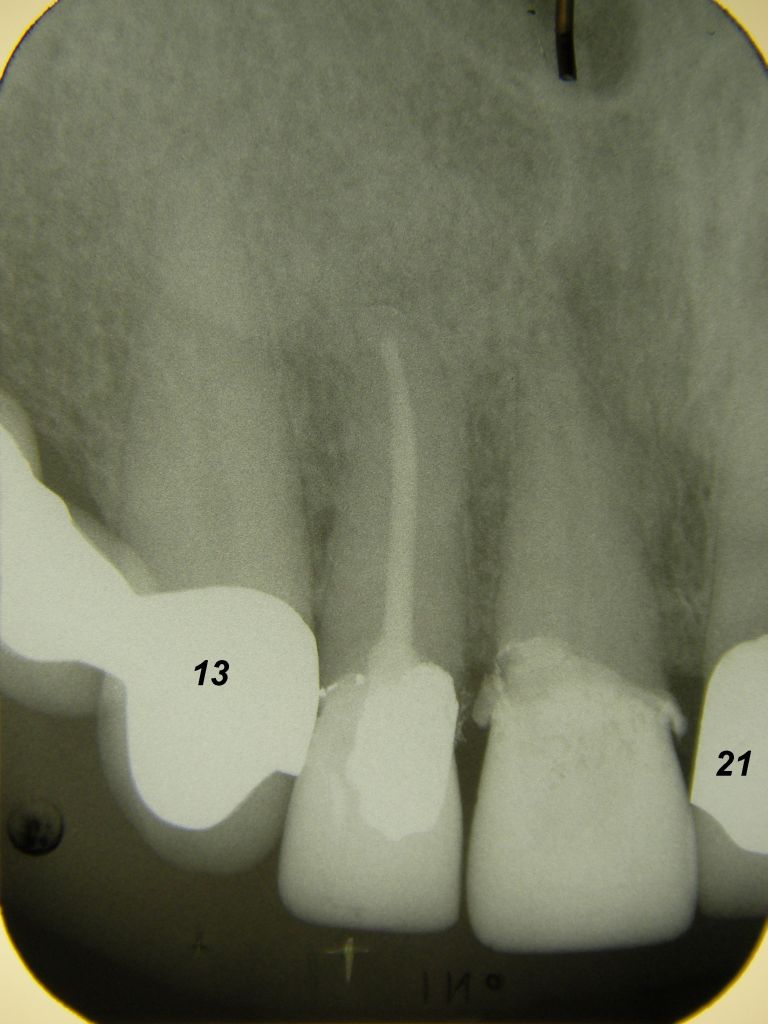

Das etwas dunkle Röntgenbild links(6/2003) zeigt diverse Probleme. Hier interessiert, daß der Zahn 22 (sprich: "zwei", "zwei") am 28.10.05 Schmerzen bereitete, weil der Zahnnerv unter Eiterbildung abgestorben war. Es brauchte 3 medikamentöse Einlagen, bis der Zahn ruhig war und am 18.11.05 eine Wurzelfüllung und einen Titanstift in den Wurzelkanal bekommen konnte. Bei der anschließenden Röntgenkontrolle rechts fiel der schlechte Randschluß der Krone 22 auf.